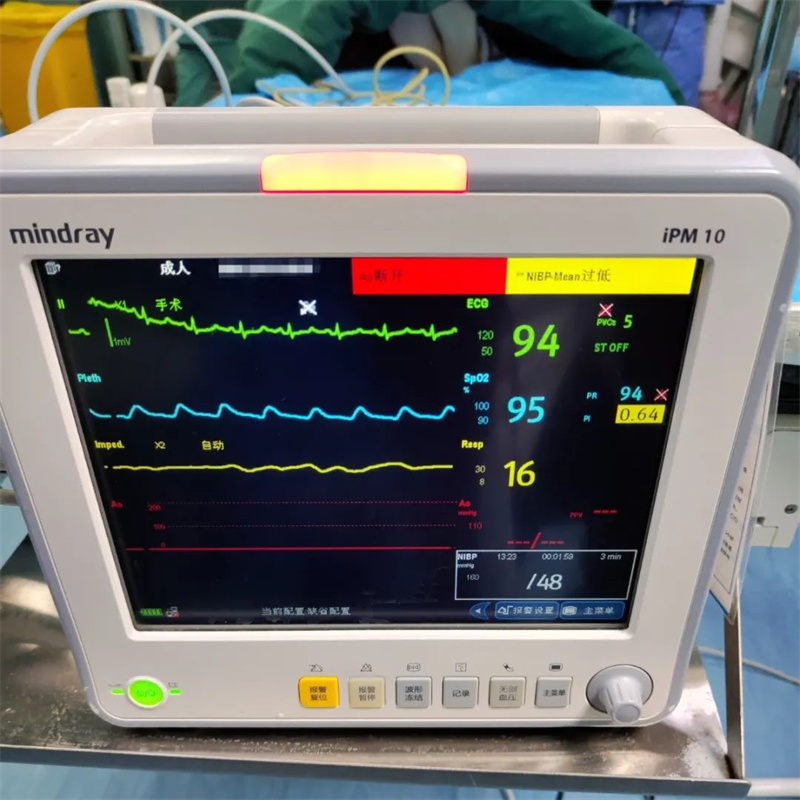

骨盆骨折、骶骨骨折、腰椎骨折、腹盆腔积血、肺挫伤、肋骨骨折、血压一度低至79/43mmHg……王女士骨盆遭受重创、多发骨折、失血性休克,凝血因子大量消耗丢失,血流动力学不稳定骨盆骨折死亡率高达60%以上。患者随时可能出现心跳停搏,病情极度危重!

在EICU严密监护下,采取损伤控制复苏策略(限制性补液、允许性低血压、平衡输血、积极做好损伤控制手术准备),脏器支持治疗至次日清晨。

王女士精神好转、面色红润,血压109/72mmHg趋于稳定,但其双下肢麻木无力,肿胀逐渐加重,考虑骨折压迫神经,行床旁超声及动脉CTA检查进一步明确患者左侧髂外静脉断裂、髂外动脉狭窄,如髂外动脉完全闭塞,下肢缺血将面临截肢风险,救治危机尚未解除。